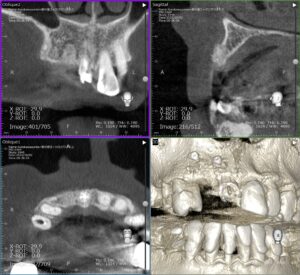

CT撮影すると骨がほとんどありません。

半年後、骨が確認できたのでインプラントを埋入しました。

骨がなくてインプラントができないようなケースでも、このように骨を造ることでインプラントが可能になります